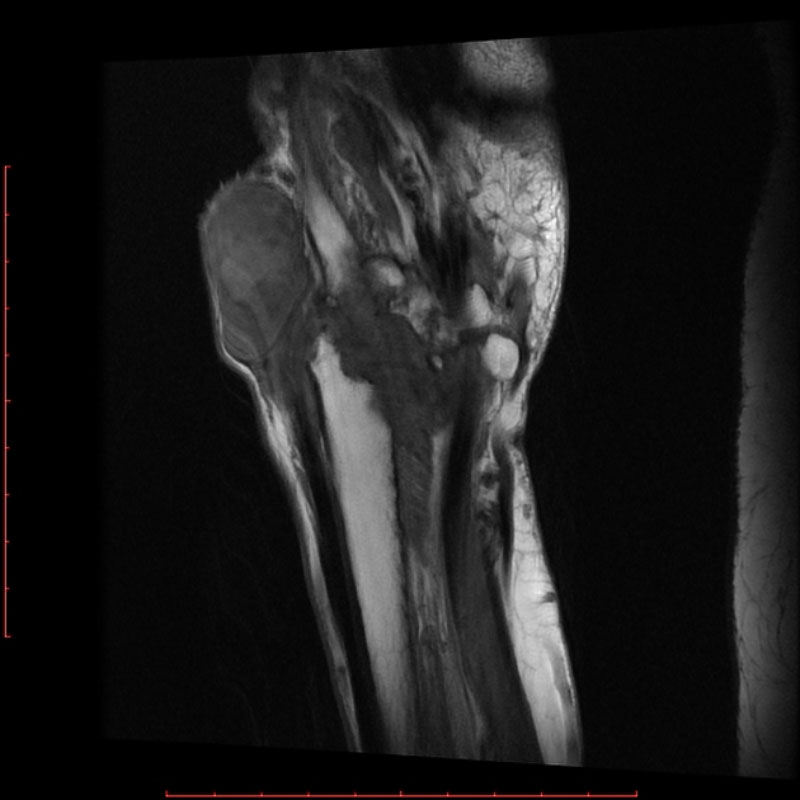

Chụp cộng hưởng từ (MRI) sử dụng từ trường và sóng vô tuyến do máy tính tạo ra để phác họa hình ảnh chi tiết về các cơ quan, mô trong cơ thể. Máy MRI được minh họa như một khối nam châm lớn. Khi người bệnh nằm bên trong, từ trường hoạt động với sóng vô tuyến và các nguyên tử hydro của cơ thể để tạo ra hình ảnh mặt cắt ngang.

Chụp MRI có thể được sử dụng để chẩn đoán các vấn đề về khớp, gồm: